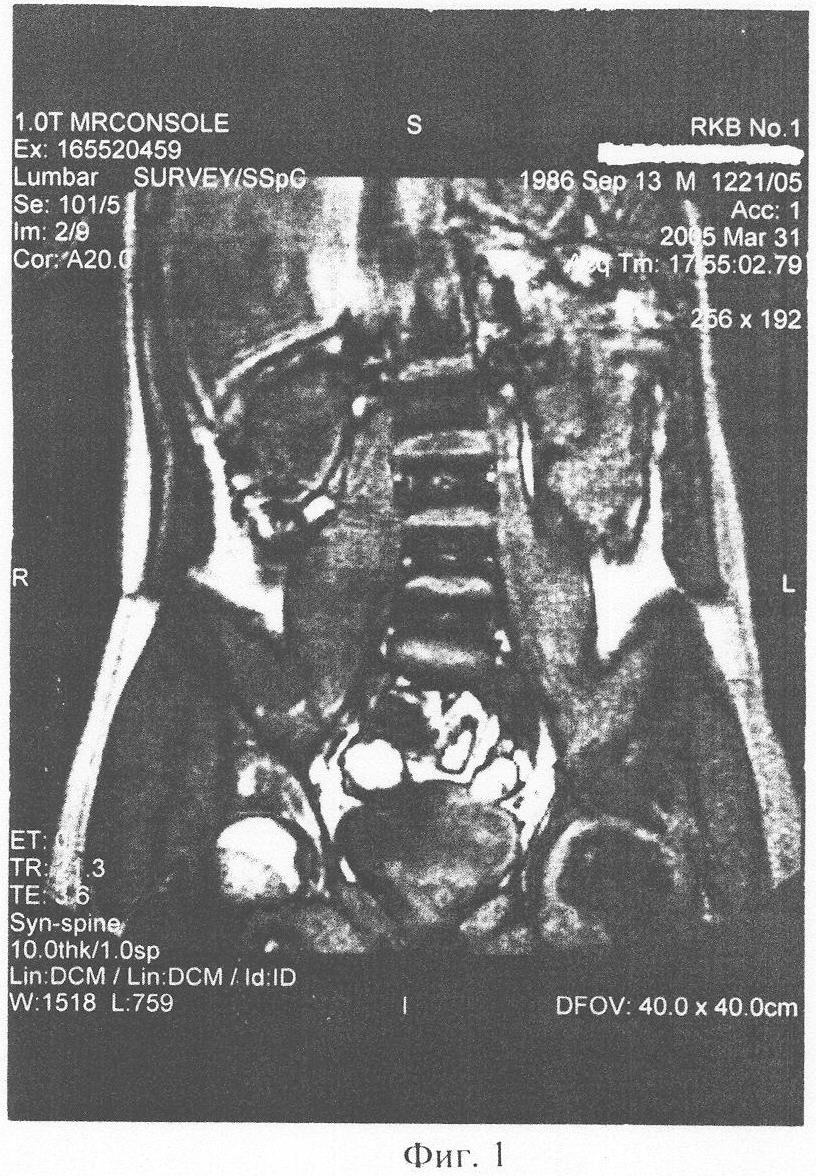

Клинический пример 1: Больной П., 19 лет, получил в ДТП травму: внутрисуставной перелом шейки левого бедра с разрывом связок и капсулы сустава. Находился 8 недель на консервативном лечении (скелетное вытяжение, иммобилизация большой тазобедренной гипсовой повязкой, облегчение осевой нагрузки костылями). Жалобы на постоянные боли в травмированном суставе, резкие боли при нагрузке сустава, резкое ограничение всех движений в суставе. Через 2,5 мес. после начала консервативного лечения боли усилились. На ЯМР-томографии (фиг.1), март 2005, выявляется асептический некроз головки левого тазобедренного сустава. Рекомендовано протезирование сустава. Был проведен 1 курс из 4-х сеансов, 1 раз в неделю: 50 мг биоматериала разводилось в 15 мл физ. раствора. Пациент укладывался в положение на здоровом боку. Весь полученный раствор вводился в виде инъекций в область trochanter major, с инфильтрацией прикрепленных к нему мышц (в энтезисы).